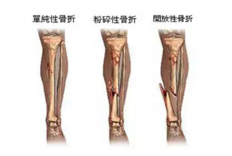

1、外傷骨頭——粗看X線片,細(xì)看CT,核磁看不清

5.png

各種外傷,如果懷疑傷到了骨頭,優(yōu)先選擇X光照片,檢查結(jié)果快速易得。若要進(jìn)一步觀察,可以選擇CT。超聲、核磁對于骨皮髓質(zhì)等看不大清,一般不選擇。